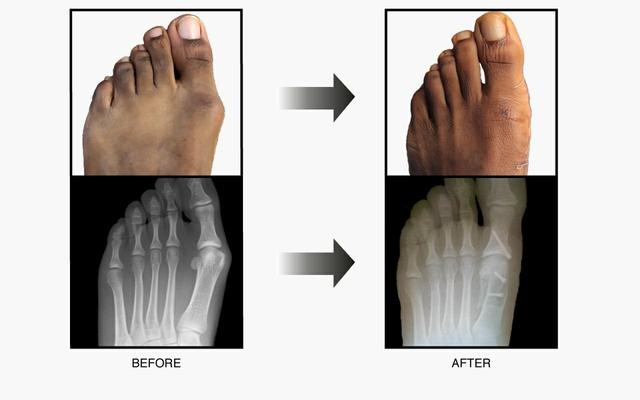

如果非手术治疗失败,可以考虑手术治疗。(证据级别:4)在选择手术前,必须确定拇外翻的严重程度。为了做到这一点,使用了负重平片射线照相术。

根据损伤的严重程度,我们可以采用以下几种外科手术:

当畸形中等至严重时,Scarf Procedure是常用的选择。从内向外沿跖骨干纵轴截骨。将跖骨头截骨块移向外侧,并用两个螺钉固定。

术后管理

对于所有的手术,病人可以在术后立即主管部分负重行走。患者需要矫形支具进行保护。对于年龄小于50岁和大于50岁的患者,雪佛龙截骨术后的长期随访显示同样的积极结果。